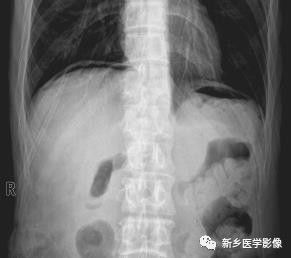

消化道穿孔x线

消化道穿孔x线,肠结核x线

消化道穿孔x线表现

消化道穿孔x线图片

胃肠道穿孔x线图片

急性胃肠穿孔x线图片

胃肠穿孔x线表现图片